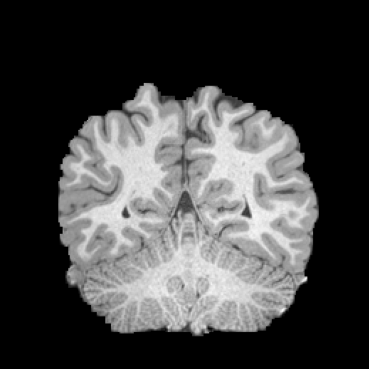

HCP Brain MRI We train on 1076 brain-extracted T1w images from the HCP dataset [24] and test on a sample of 100 pairs between 36 images via mean Dice over 28 midbrain structures [20, 21]. We train and execute the network at [130155130], then compute the Dice score at full resolution.

OASIS Brain MRI We use the OASIS-1 [12] data preprocessed by [9]. This dataset contains images of 414 subjects. Following the data split in [14], we train on 255 images and test on 153 images555Due to changes in the OASIS-1 data, our test set slightly differs from [14]. We evaluate all methods using our testing protocol so that results are consistent.The images in the dataset are of size [160192224], and we crop the center of the image according to the preprocessing in [14], leading to a size of [160144192]. During training, we sample image pairs randomly from the train set. For evaluation, we randomly pick 5 cases as the fixed images and register all the remaining 148 cases to the 5 cases, resulting in 740 image pairs overall.